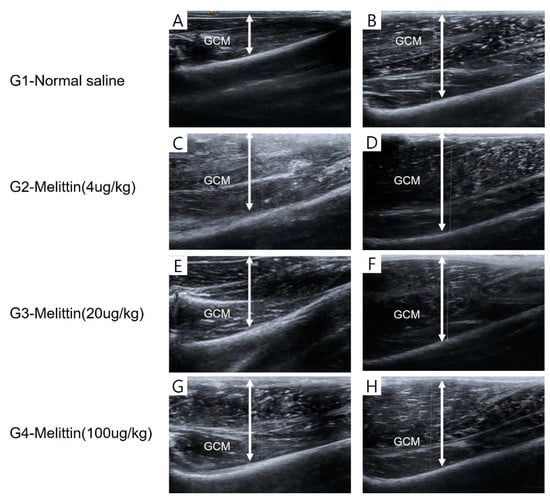

The greatest length measured using a tape around circumference of the calf regions was determined, with the rabbits’ knee joints bent at a 90-degree angle and the ankles relaxed. The thickness of both sides of the GCM in the longitudinal plane was evaluated from the outermost layer to deep fascia using real-time B-mode ultrasound imaging (Figure 11). The pictures of the GCM were captured at the predetermined points corresponding to the injection sites on the mentioned sides of the muscle.

Figure 11. The thickness of the GCM (gastrocnemius muscle) was measured using ultrasound, defined as the distance between the superficial and deep aponeuroses of the GCM muscle, indicated by up–down arrows. The provided images are representative longitudinal sonograms of the right (A,C,E,G) and left (B,D,F,H) GCM muscles.